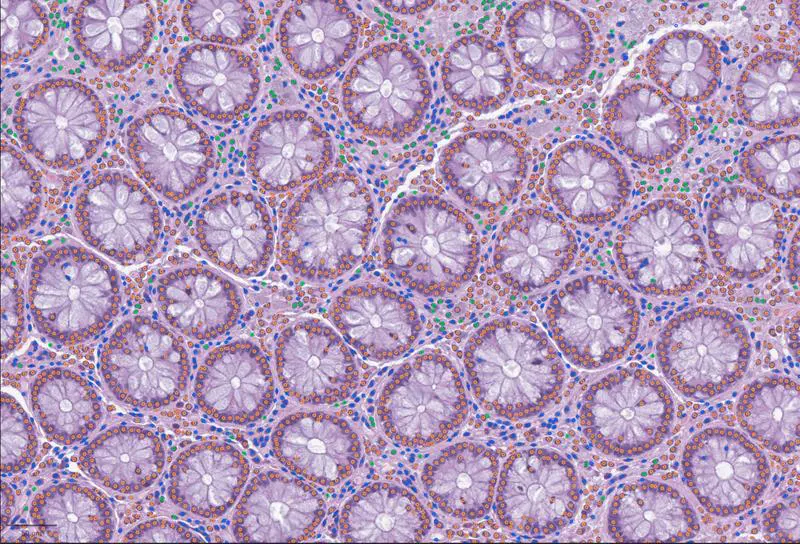

Whole-Slide-Bilder, die ganze Gewebeproben in höchster Auflösung abbilden, enthalten enorme Mengen biologischer Information – von der Gesamtarchitektur bis hin zu einzelnen Zellen. Trotz zunehmender Digitalisierung in Pathologie und Forschung blieben diese Daten bisher schwer systematisch auszuwerten und mit anderen Datentypen wie Genexpressionsprofilen zu verknüpfen. Häufig liegen sie in proprietären Formaten vor und sind nur mit spezifischen, oft inkompatiblen Programmen bearbeitbar.

LazySlide nutzt sogenannte Foundation Models – große, auf umfangreichen Datensätzen vortrainierte KI-Modelle – um Whole-Slide-Bilder in kleinere, handhabbare Abschnitte zu zerlegen und automatisch zu analysieren. Die Software erkennt Gewebemuster, identifiziert Zelltypen, quantifiziert strukturelle Veränderungen und verbindet visuelle Merkmale direkt mit molekularen Daten, ohne dass umfangreiche manuelle Annotationen notwendig sind.

Eine besondere Stärke der Software ist die Verknüpfung mit natürlicher Sprache. Forscher können gezielte Fragen stellen – etwa wo in einer Probe Anzeichen von Verkalkung, Entzündung oder Tumorinvasion auftreten. Die KI hebt entsprechende Regionen hervor und liefert quantitative Bewertungen. Zudem ermöglicht LazySlide Zero-Shot-Analysen: Das Tool erkennt beispielsweise das Ursprungsorgan einer Probe oder unterscheidet gesundes von krankem Gewebe, ohne dass es für jede Fragestellung neu trainiert werden muss.